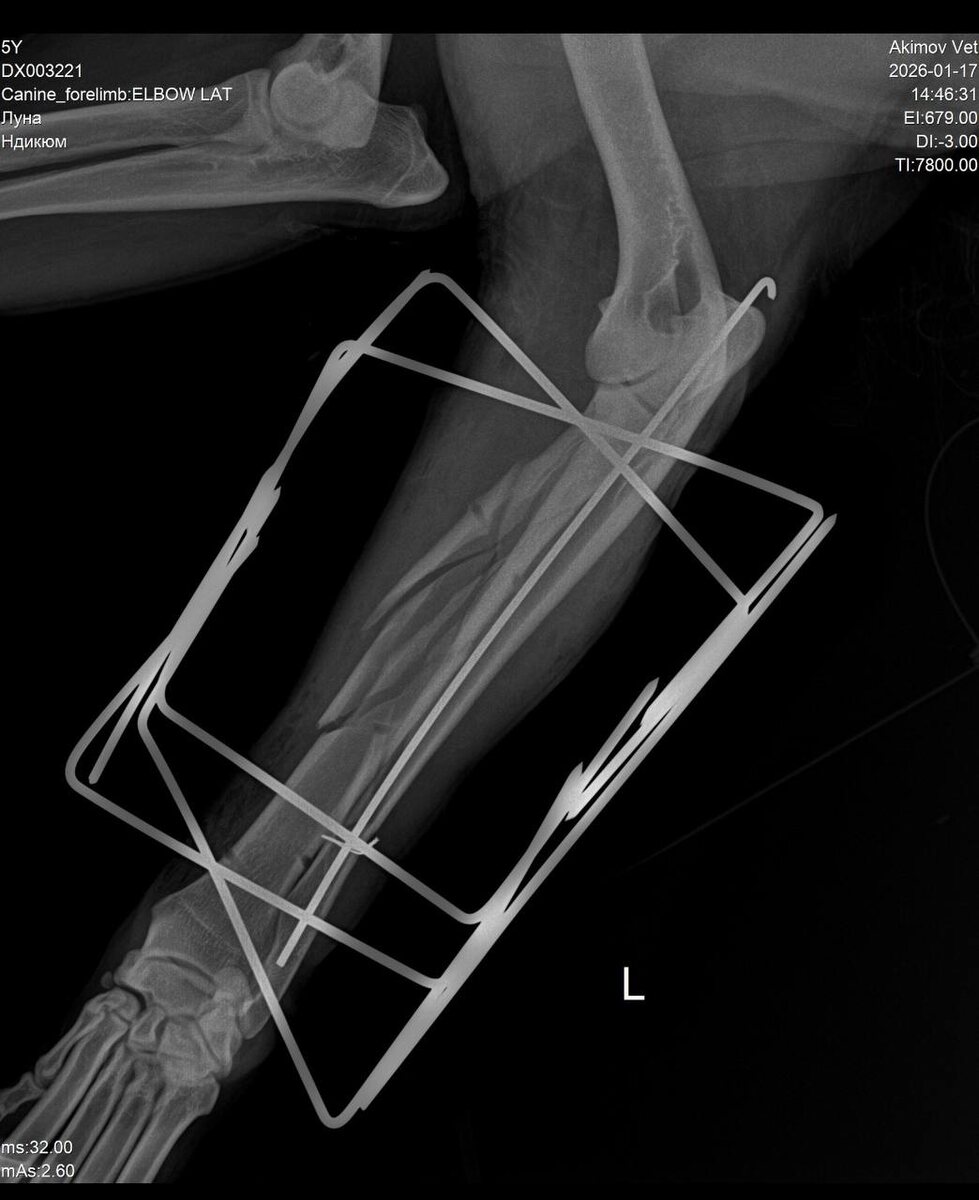

Расскажу немного про Луну. Сделали операцию - остеосинтез предплечья. Прогнозы осторожные, но уже положительные. Потихоньку гуляем и пользуемся лапой. Обработки и таблетки по расписанию. Далее по плану у нас снятие швов, приемы, ежемесячные снимки, реабилитация. Покой и ограничение нагрузок по умолчанию🧘🏻‍♀️ #Луна конечно не очень рада. Скакать было веселее. Верю что общими усилиями она продолжит свой может не такой как раньше активный быт. И еще полноценно поплаваем в любимом водоеме, погуляем по лесу и поиграем в ее любимый мячик. Будем стараться !

На последнем изображении снимок конструкции